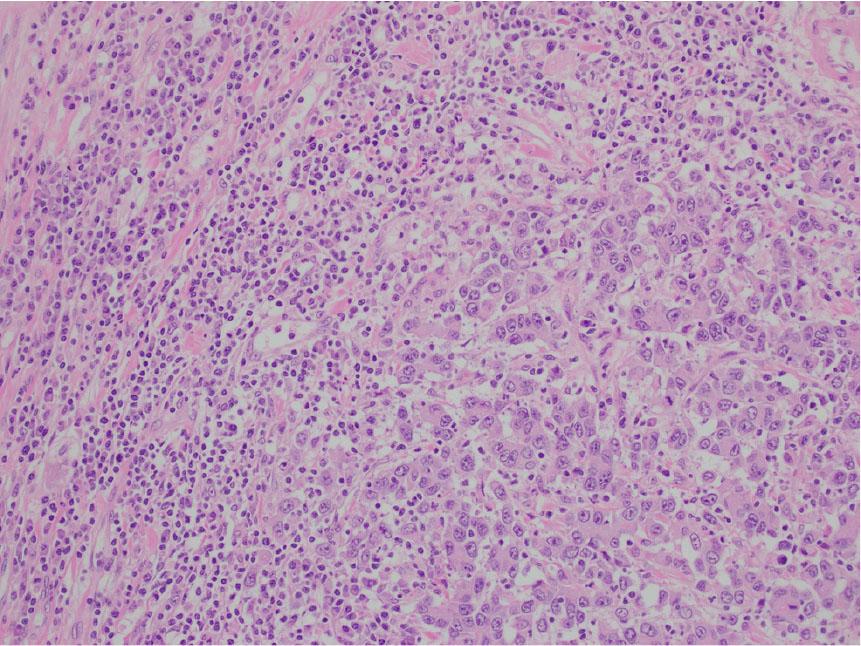

Figure 3: